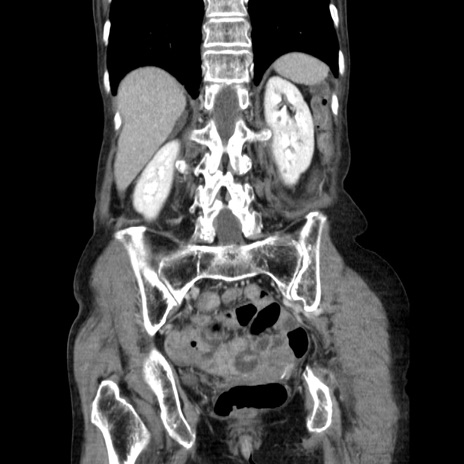

症例25(冠状断像)

【症例】80歳代女性

【主訴】胸のつかえ感

【現病歴】約9時間前に食後から胸のつかえた感じあり、嘔吐あり、来院。

【既往歴】胃癌(全摘)、胆摘、虫垂炎

【身体所見】心窩部に圧痛あり、反跳痛なし。

【データ】WBC 5700、CRP 0.05